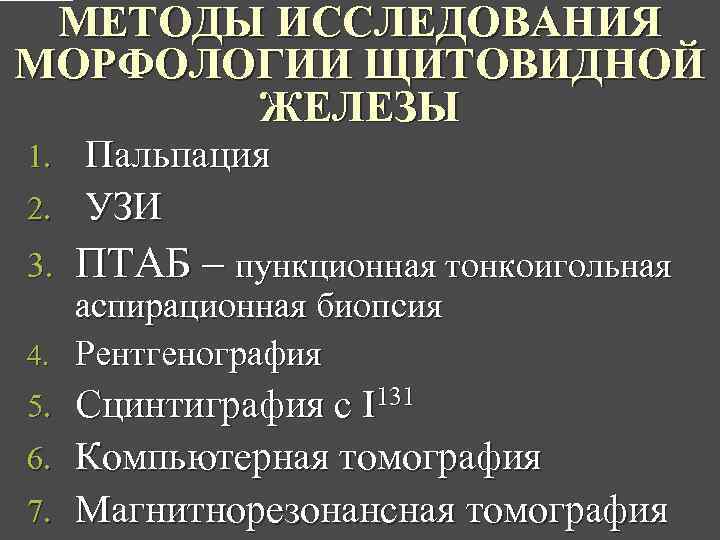

МЕТОДЫ ИССЛЕДОВАНИЯ МОРФОЛОГИИ ЩИТОВИДНОЙ ЖЕЛЕЗЫ Пальпация 2. УЗИ 1. 3. ПТАБ – пункционная тонкоигольная аспирационная биопсия 4. Рентгенография Сцинтиграфия с I 131 6. Компьютерная томография 7. Магнитнорезонансная томография 5.